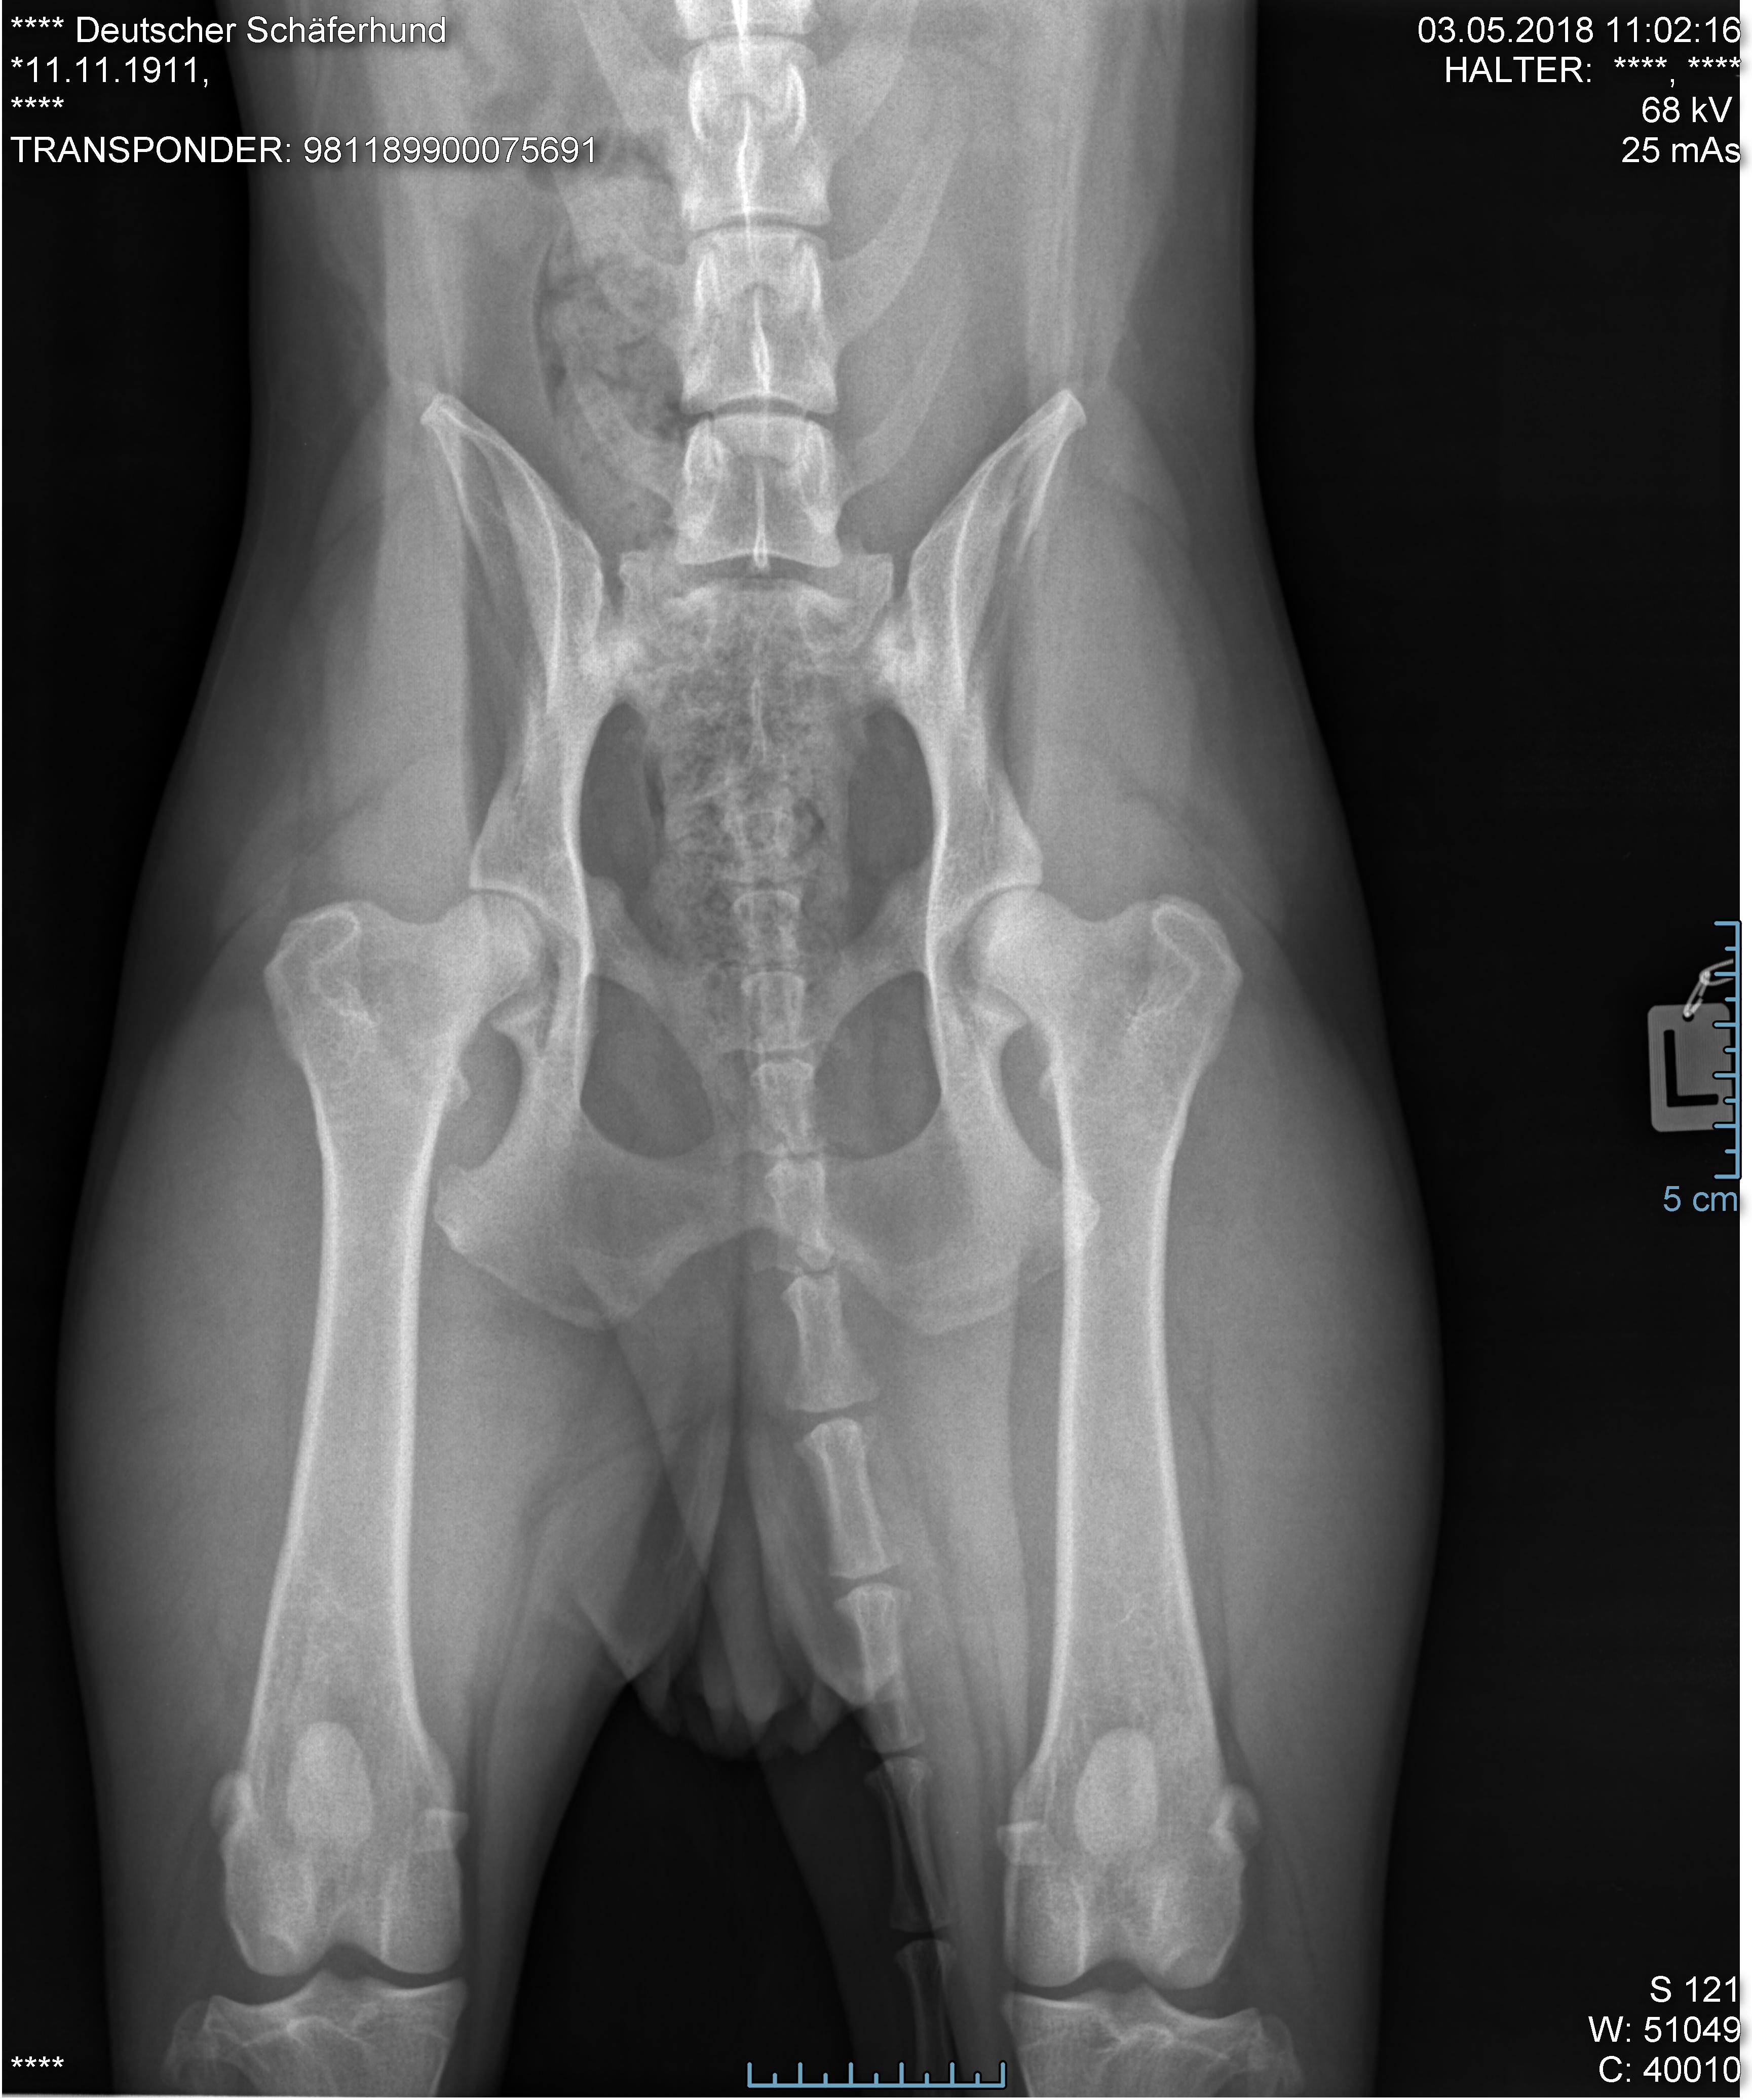

Foto von Diego`s Hüfte